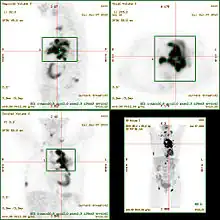

Le SUV est souvent utilisé pour caractériser la fixation du Fluorodéoxyglucose (FDG) dans un tissu, un organe ou une lésion en tomographie par émission de positons (TEP). Il intervient au moment de l'analyse des images TEP, réalisées avec une injection préalable de FDG à un patient.

Si la valeur du SUV vaut 1, cela signifie que le radiopharmaceutique est réparti de façon homogène dans tout le patient considéré. Tout écart à cette valeur signifie que la répartition du traceur n'est pas uniforme. Le corps humain fixant le glucose de façon très hétérogène, cela permet lors d'un examen de distinguer les différentes structures anatomiques et processus fonctionnels dans les images réalisées. Un SUV élevé peut par exemple indiquer un hypermétabolisme anormal, souvent associé à la présence d'une tumeur.